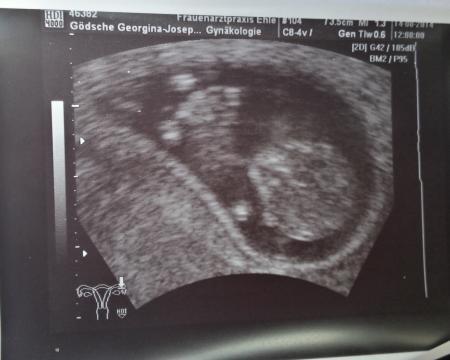

Melodie55

7 SSw ich bin so gespannt der nächste Termin ist in 3 Wochen. Wie sehen eure aus? :))

Bild zu Ich zeige meins, zeigst du mir deins? - Forum für März - Mamis